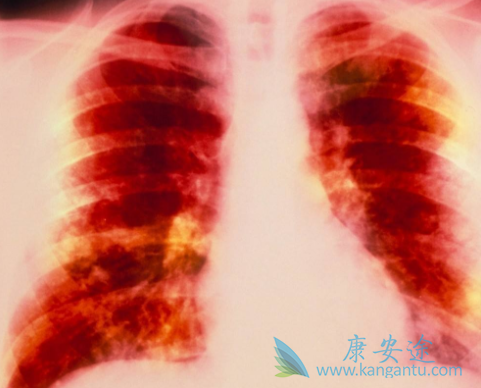

随着现代医学对肺癌的不断深入了解,越来越多的治疗方法被应用到临床治疗中,传统的手术、放化疗手段不断优化,新型的靶向治疗、免疫疗法层出不穷。因此肺癌的治疗也逐步进入了精准治疗时代,尤其是有特定基因突变的晚期肺癌患者,相应靶向药物治疗是首选。特罗凯(厄洛替尼)就是一款针对EGFR突变的肺癌靶向药,那患者服用特罗凯后身体会有哪些变化呢?